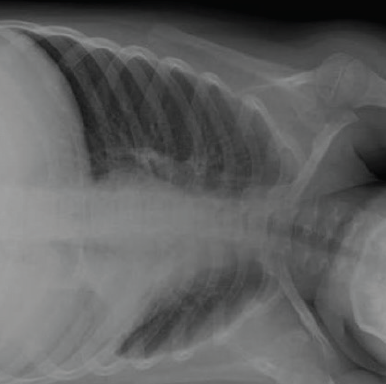

Chest radiographs taken in our ED were remarkable for an opacity in the left lower lobe on posteroanterior view (Figure 3) and lateral view (Figure 4), with significant hyperinflation of the boy’s right lung. Left lateral decubitus view showed an incomplete collapse of the left lung (Figure 5).

Figure 3. Posteroanterior chest radiograph of a 7-year-old boy with persistent cough showing an opacity in the left lower lobe and hyperinflation of the right lung.